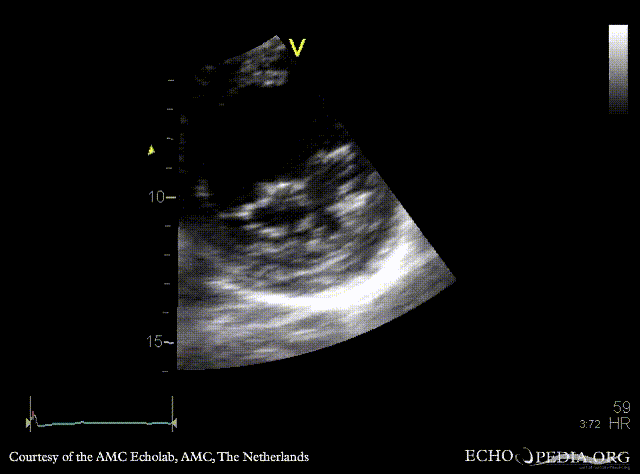

| PSAX: thickend mitral valve leaflets, prolaps of PMVL